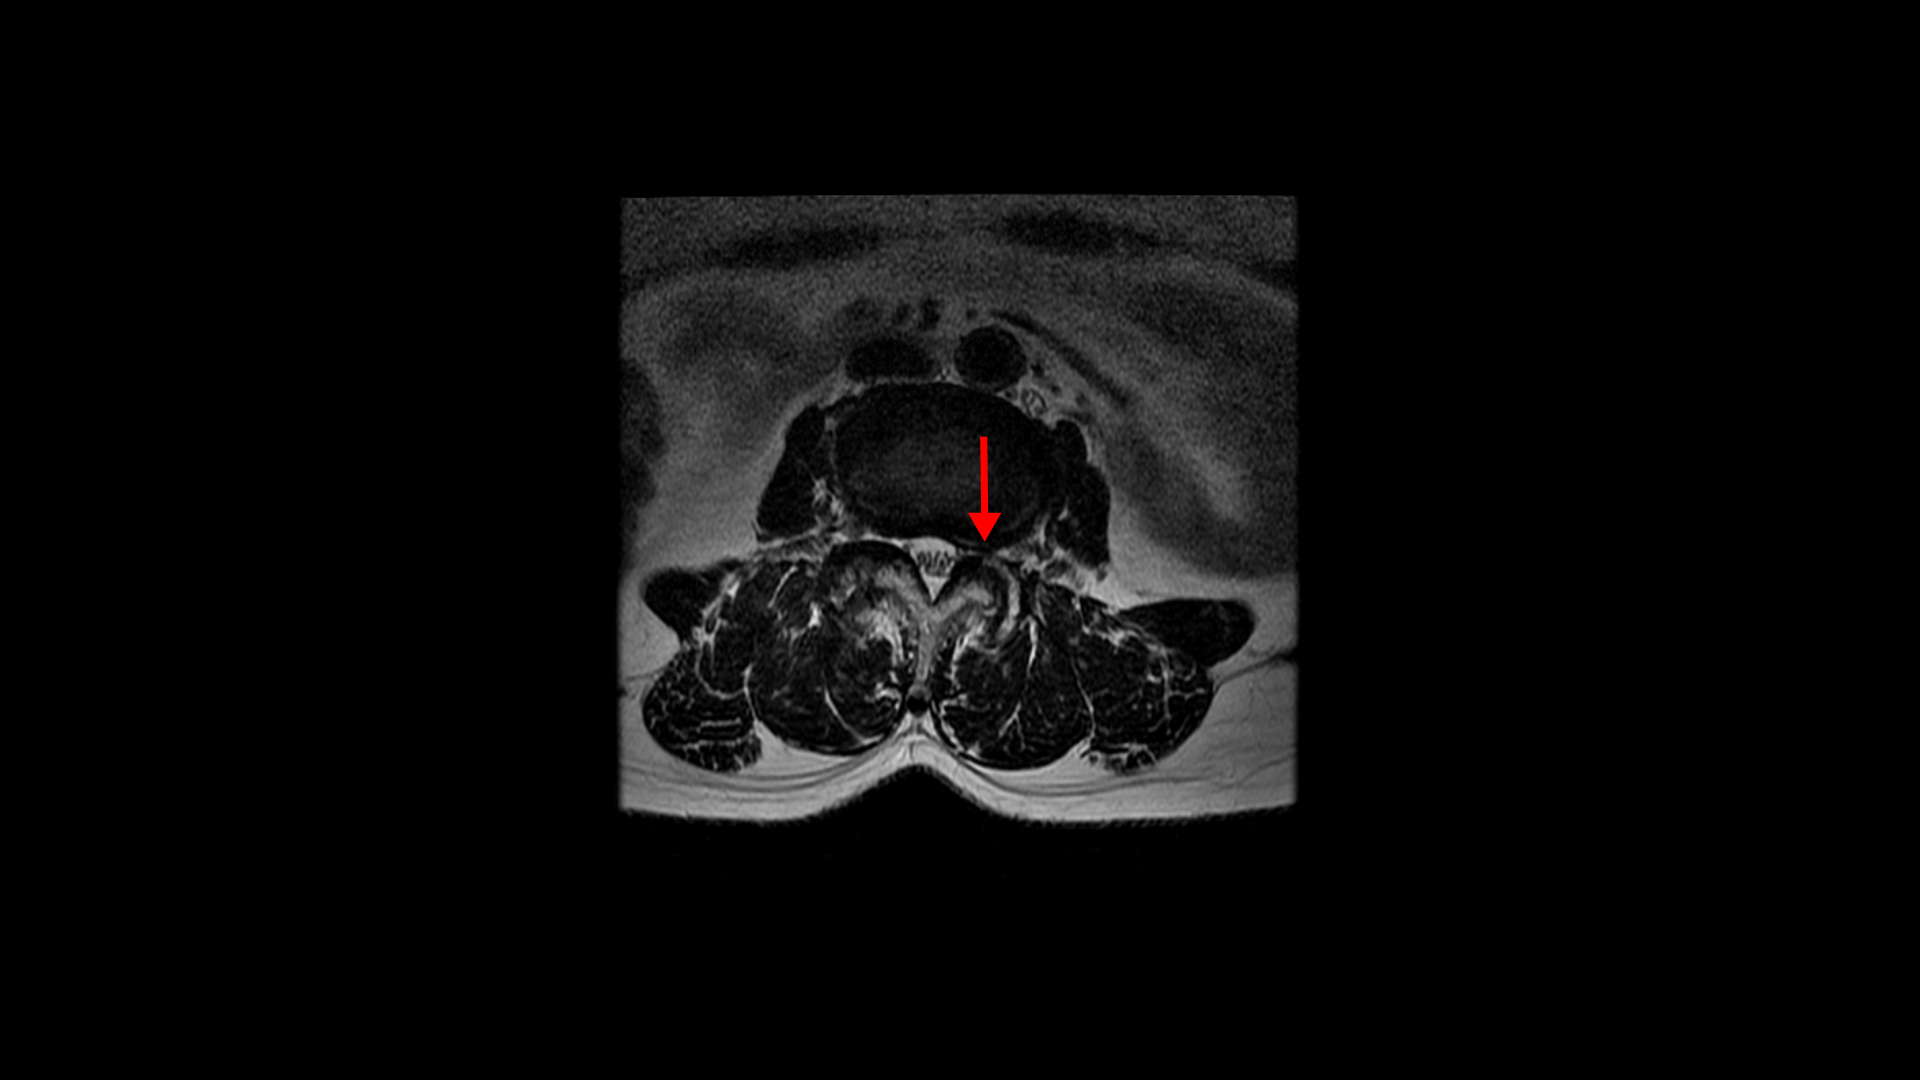

그런데 이 환자분의 제일 불편한 증상은 왼쪽이 아니고 오른쪽 엉치와 다리 증상입니다. 이분 오른쪽 신경 구멍들을 보면 전부 다 넓게 잘 열려 있습니다.

엉치와 다리 방사통을 일으킬만한 특별한 신경 눌림이 보이지 않는 것입니다. 그럼에도 불구하고 여러 마디의 전방전위증과 척추관 협착 그리고 디스크 탈출이 있으니까 그것을 원인으로 보고 신경 주사도 맞고 시술도 받으셨습니다. 그러나 별 효과는 없었습니다. 그리고 대학병원에서도 결국은 수술밖에 방법이 없다고 수술을 권유하였습니다.

이 환자분은 MRI에서 오른쪽에 신경 눌림이 심해 보이지 않는 상태에서 오른쪽에 심한 방사통과 함께 오른쪽 중둔근이 극심하게 뭉쳐있는 것이 확인되었습니다. 만일 이 근육들을 풀어서 하룻밤 사이에 방사통이 사라진다면 그건 명확히 근육성 방사통이었던 겁니다. 보통 단단하게 뭉쳐있는 근육에 의한 방사통이라해도 하루만에 치료가 되는 경우는 매우 드뭅니다. 특히 7년씩이나 방사통이 있었으면 근육이 뭉쳐도 정말 심하게 뭉쳐있을 거고 엉덩이 근육만이 아니라 허리 근육 및 다리 근육들도 다 뭉쳐있을 가능성이 높기 때문에 1-2주 정도 매일 4-5회 이상 다양한 방법으로 근육을 풀어주면서 쉬는 걸 반복하는, 즉 풀어주고 쉬고 풀어주고 쉬고 풀어주고 쉬고를 반복해야 극심하게 뭉친 근육이 풀립니다. 그래야 방사통이 사라지고 좋아지는 겁니다.